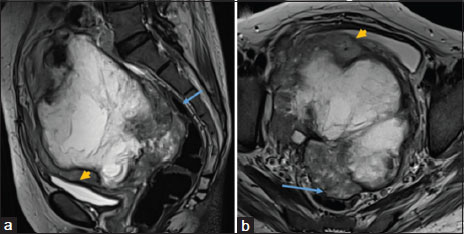

She was wheel chair bound due to weakness when she first attended our center. There was mild pallor and Grade 2 pitting edema. Her vital parameters were within the normal range. On abdominal examination, she had firm, fixed, nontender abdominal mass extending from the pelvis up to the umbilicus. The vaginal vault and rectal mucosa were smooth on pelvic examination. Her complete blood count, coagulation profile, liver, and renal functions were normal. Her CA125 was mildly raised (68U/ml), and carcinoembryonic antigen was normal. Lower limbs Doppler ruled out any deep-vein thrombosis. Cystoscopy revealed bladder mucosal involvement in proximity to the urethral orifice. Magnetic resonance imaging suggested 15.5 cm × 13 cm × 15 cm heterogeneous pelvic mass displacing urinary bladder anteriorly and rectum posteriorly with no luminal involvement. The mass was hyperintense on T2, hypointense on T1 with multiple hypointense septations and irregular loculi with nodular walls with T2 intermediate intensity [Figure 1]a and [Figure 1]b. There was bilateral hydronephrosis [Figure 2]. Computed tomography (CT) of the thorax revealed bilateral minimal effusion and no evidence of metastasis. Histopathology review of previously done biopsy done at our institute revealed a spindle-cell tumor with mild atypia, no significant mitotic activity along with the areas of infarction. Immunohistochemistry (IHC) was sparsely positive for desmin and occasional cells showed S-100 expression while negative for beta catenin, CD34, caldesmon, DOG1, CK, c-kit. In view of lack of severe atypia and lack of mitotic activity and noncontributory IHC, a diagnosis of a spindle-cell neoplasm was offered. A repeat ultrasound-guided biopsy was done at our institute which showed similar histopathologic findings. No morphologic features of high-grade pathology were seen [Figure 3]a. In view of her age, possible low-grade tumor and a symptomatic pelvic mass decision were taken for the surgical removal of mass which would entail total pelvic exenteration. Patients and relatives were counseled regarding the procedure, surgical outcome and postoperative morbidities.{Figure 1}{Figure 2}{Figure 3}

| Figure. 1Magnetic resonance imaging of the pelvic mass with loss of planes with bladder (arrowhead) and rectum (arrow) (a) sagittal view (b) axial view